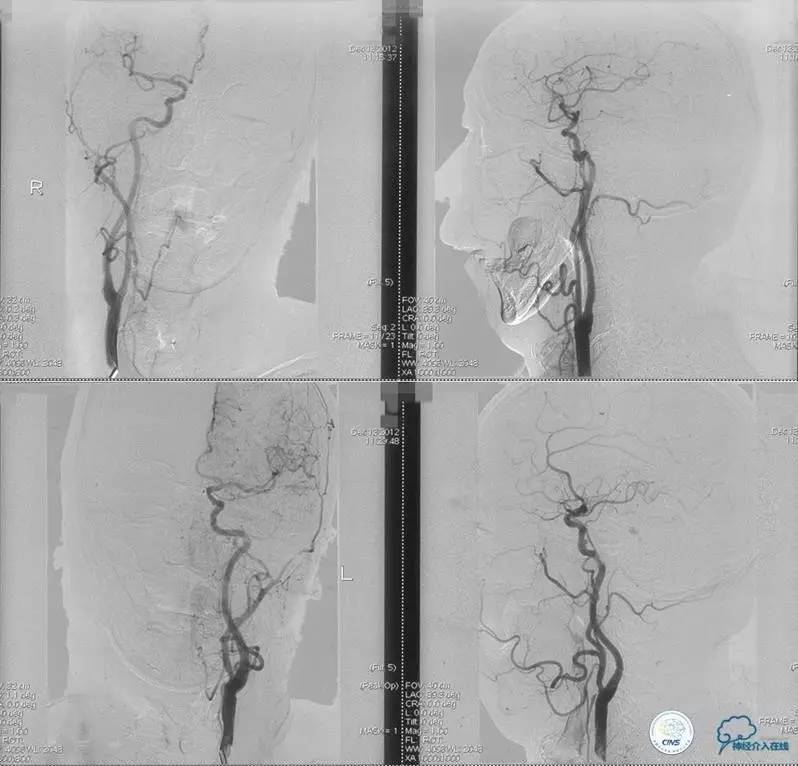

术前DSA

▼2013-12-13